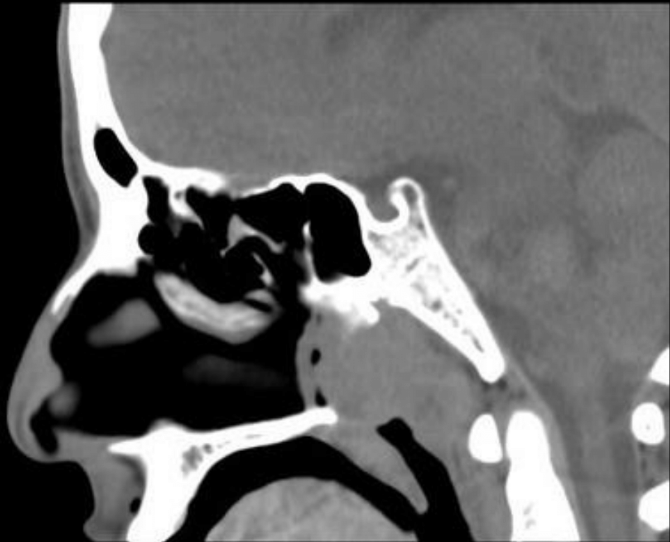

CT y qué observas

A

CT con reconstrucción sagital

Se ve oclusión de la nasofaringe